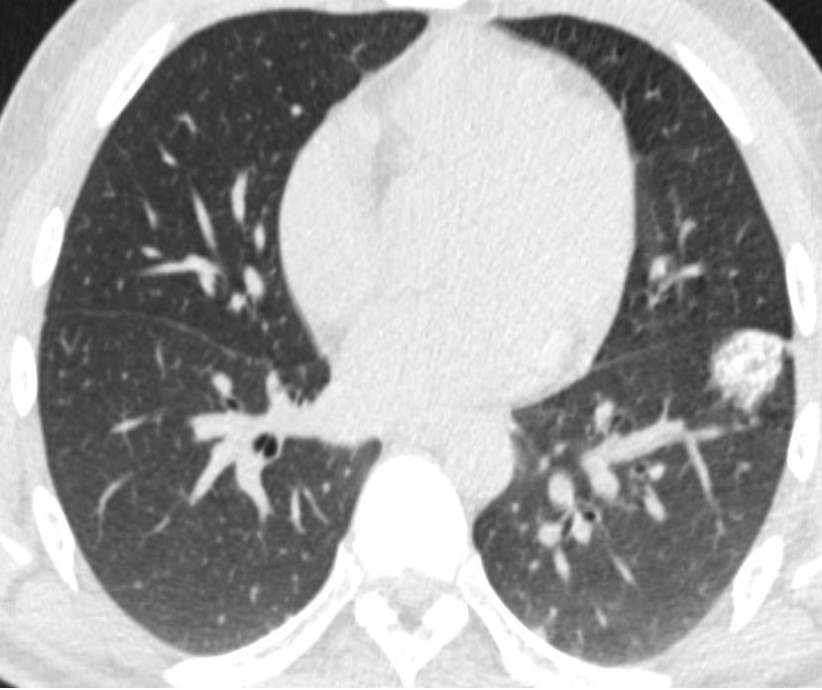

1. 新的活逐渐增大的实性孤立性结节或肿块 A new or enlarging solitary nodule or mass

这是影像引导肺活检最常见的适应证,一般人群中约8.5%的人偶然发现肺结节,有危险因素的受试者中高达50%的人偶然发现肺结节

1) A new or enlarging solitary nodule or mass

2) Multiple nodules in a patient without known cancer or in prolonged remission